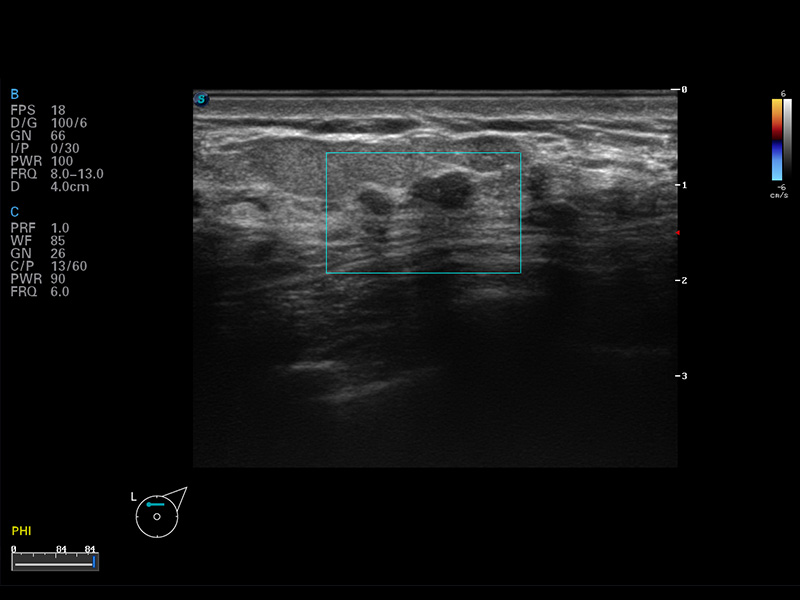

S8 EXP便携式彩色多普勒超声诊断仪是乐玩lewin国际研发的高端全身应用型便携彩超。高通道的VIS平台融合可视化(Visual)、智能化(Intelligent)和人性化(Smart)的特点,配以乐玩lewin国际自主研发生产的探头大家族,使您能够快速、准确的获得病人信息,提高工作效率的同时减轻疲劳。

谐波成像